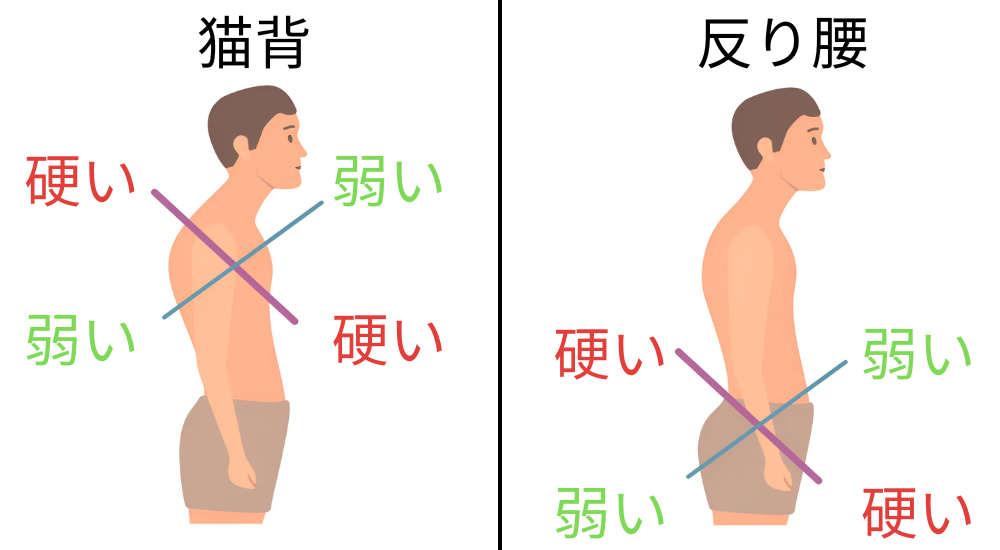

私たちの身体は、重力に対してバランスを取りながら立ったり座ったりしていますが、猫背や反り腰、左右どちらかに重心が偏るなど、偏った姿勢を続けると、特定の筋肉や筋膜に継続的に過剰な負担がかかります。

例えば、猫背の姿勢では、背中の筋肉(特に脊柱起立筋や菱形筋)が常に引き伸ばされた状態になり、逆に身体の前面(大腰筋や腹筋群)は縮こまりやすくなります。

このような筋肉のアンバランスが生じると、関連する筋膜も引っ張られたり縮んだりして、柔軟性を失い硬くなっていきます。

硬くなった筋膜は、その部位だけでなく、筋膜の繋がりを介して離れた部位にも影響を及ぼします。

例えば、腰部の筋膜の硬さが股関節の動きを制限したり、逆に股関節周りの筋膜の硬さが腰に負担をかけたりすることもあります。

このように、姿勢の悪さから生じる筋肉のアンバランスが筋膜の癒着や硬化を招き、それが血行不良や痛み物質の蓄積を引き起こし、最終的に腰痛として現れるのです。